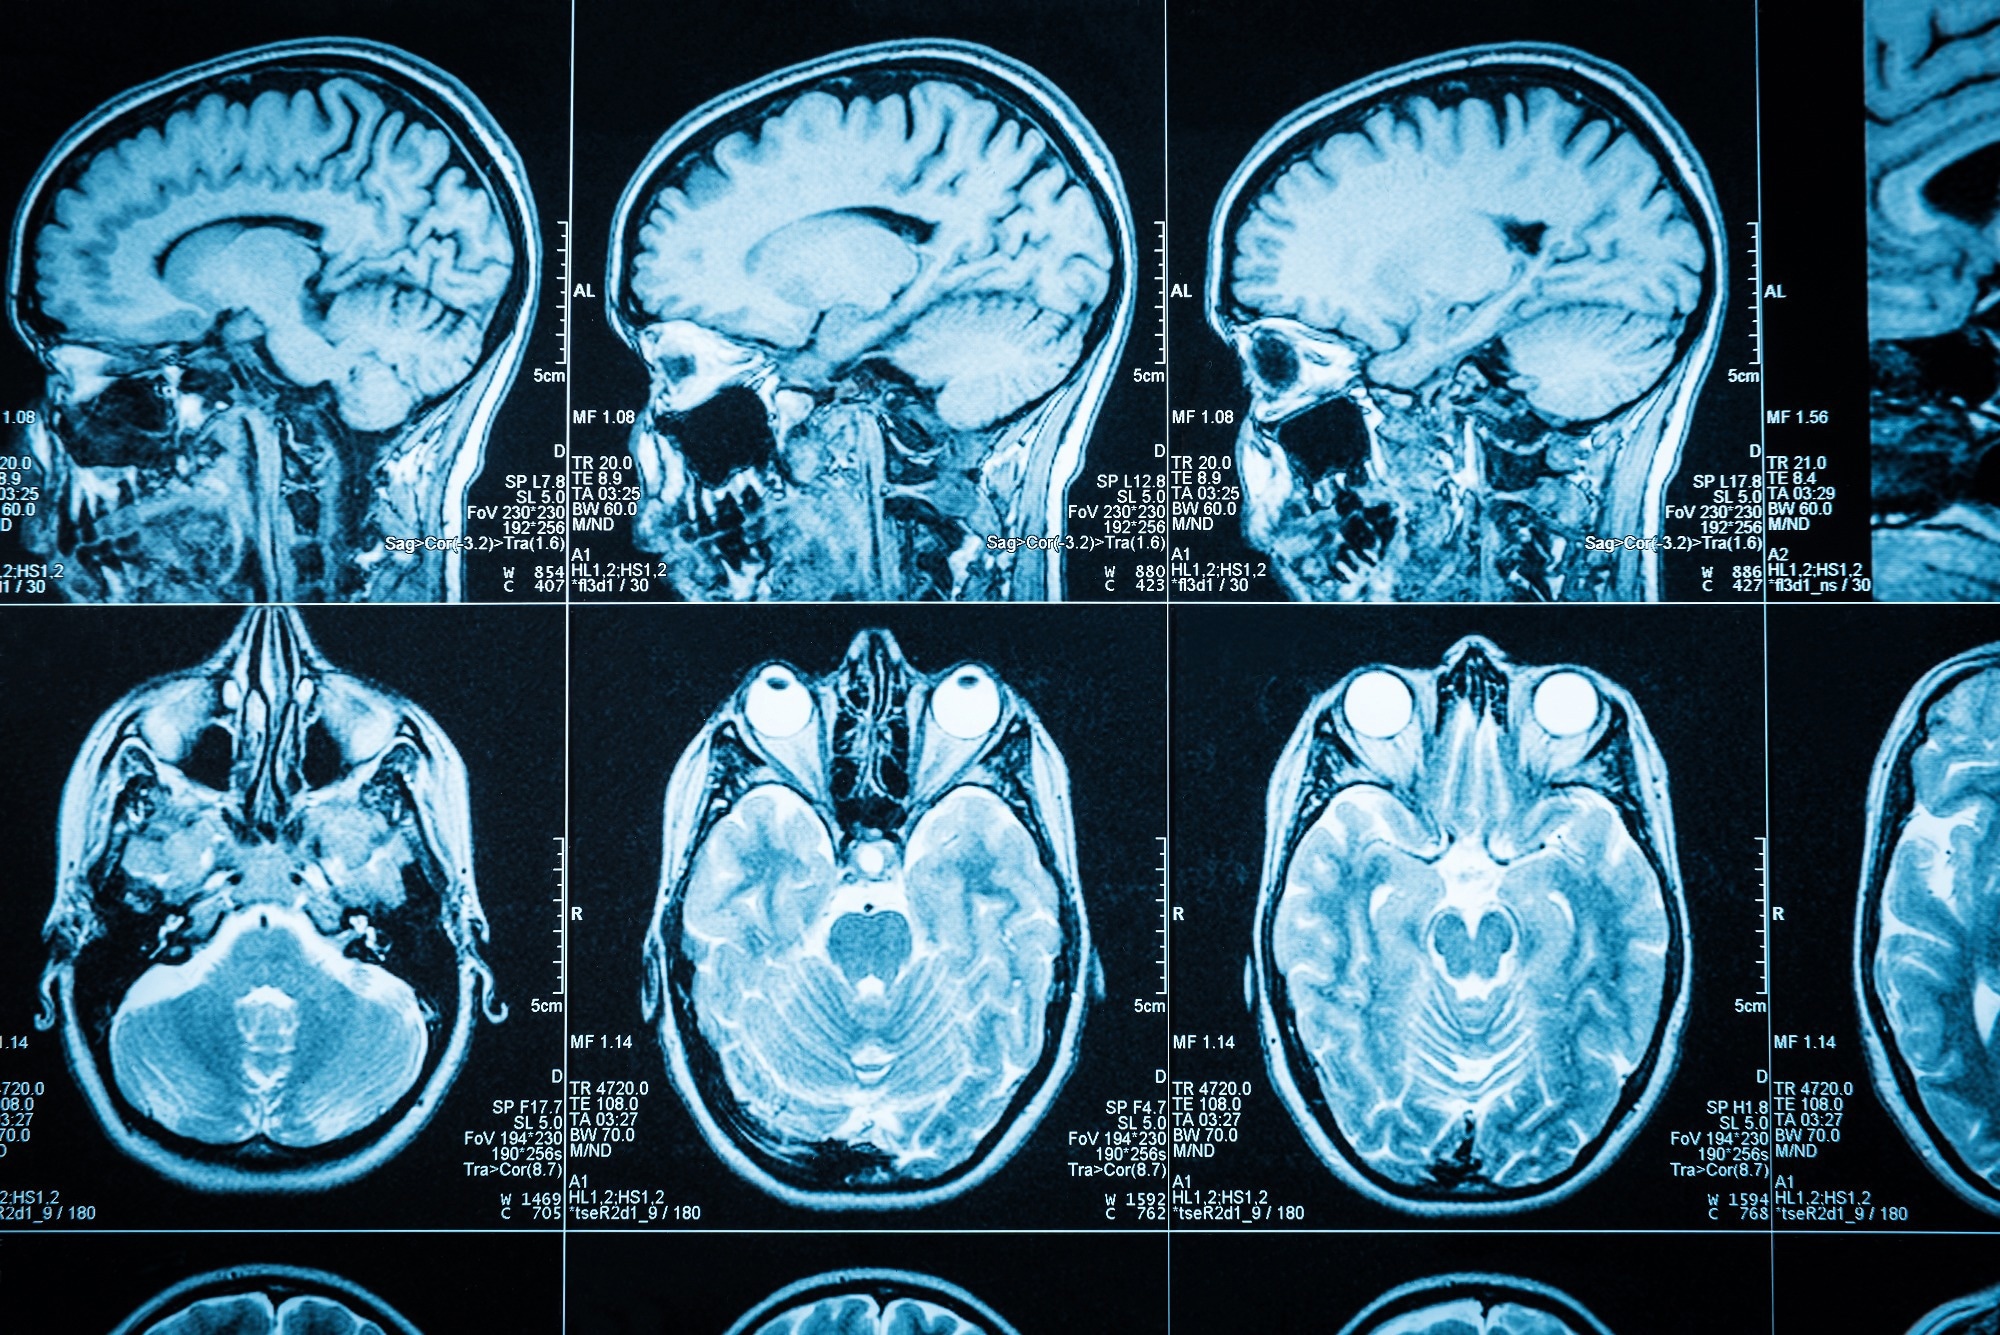

Image Credit: Triff/Shutterstock.com

The diagnosis is commonly suspected on MRI with focal spinal cord displacement/buckling and, less frequently, on the direct sight of a cystic formation inside the spinal canal with signal patterns comparable to those of CSF.

CT myelography, which may also diagnose the degree of free-flowing CSF between the arachnoid cyst and the main subarachnoid space, can typically provide better delineation.

With the widespread use of MRI, many lesions are now discovered by chance. MRI pinpoints the position and extent of spinal cord compression, but CT myelography (CTM) pinpoints the dural defect through which an extradural cyst communicates with the subarachnoid area.